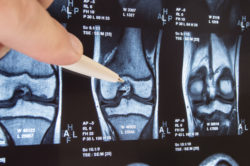

Zimmer Persona knee replacement knee implant knee joint MRIA 2015 Zimmer Persona recall over a reportedly defective device component has affected thousands of implants in use across the country.

The Zimmer Persona recall was issued over its tibial plate component, which a number of patients have reported caused side effects or device failure. The U.S. Food and Drug Administration (FDA) responded, issuing its Zimmer Persona recall to prevent further injury. But many patients are still implanted with these devices, and therefore still at risk of suffering from side effects of the defective component.

Knee replacement surgery is one of the most common surgical procedures in the U.S. In fact, around 600,000 U.S. patients undergo knee surgery each year. Unfortunately, knee implants can reportedly have serious side effects on their users.

Patient reports of complications with their knee implants are more serious than simple wear and tear. Instead, they involve more serious side effects, including tibial implant failure. Failure of a knee implant can lead to some serious complications and, in some cases, may even require removal surgery.